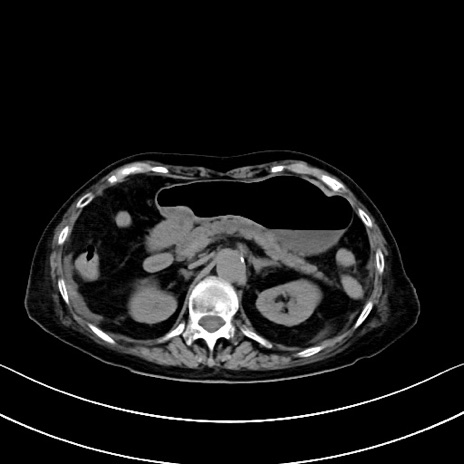

他院CT

横断像